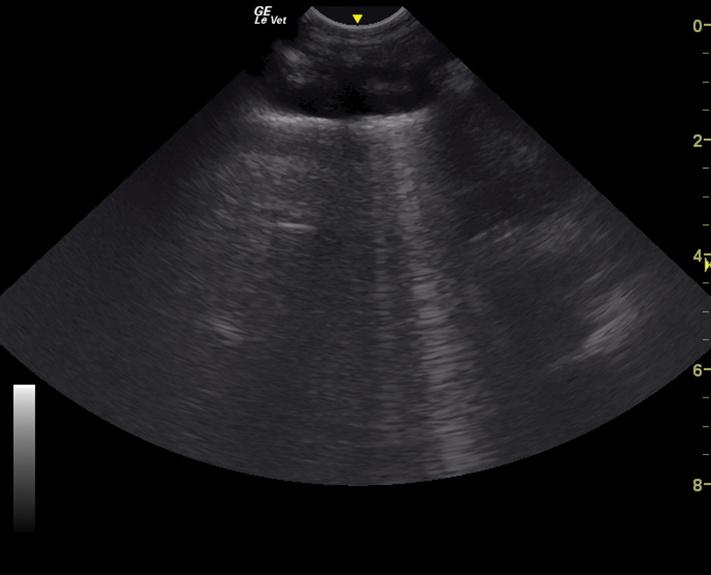

Thoracic ultrasound, also known as thoracic focused assessment with sonography for trauma, triage, and tracking (TFAST), allows clinicians to assess for pleural

and pericardial effusion, pneumothorax, and pulmonary parenchymal infiltrates [15–20]. It is particularly useful in patients that are not stable enough for thoracic radiographs, as well as a monitoring tool to assess for response to therapy. Thoracic ultrasound may be performed with the patient in sternal or lateral recumbency. Pleural effusion is generally visible in the cranial and/or caudoventral pleural space. Ultrasound guidance to localized fluid pockets can be helpful to guide thoracocentesis. When evaluating for the presence of pneumothorax, the caudodorsal thorax is evaluated for the lack of a “glide” sign, which is diagnostic for pneumothorax. A glide sign is created by the normal back and forth respiratory motion of the interface between the visceral and parietal pleura (Video 1.1). Free air in the thoracic cavity obliterates the glide sign [15–17]. Cellular or fluid infiltrate into the pulmonary parenchyma, as with edema, hemorrhage, and pneumonia can be assessed using ultrasound in four windows in each hemithorax (caudodorsal, cranial, middle lung lobe regions, and perihilar) for the presence of increased penetration of ultrasound, which manifest as hyperechoic lines (B-lines) in parallel with the ultrasound beam, that can be individual or coalescing (Figure 1.4 and Video 1.2) [18–22].

Video 1.2 TFAST showing coalescing B-lines created by marked pulmonary infiltrates allowing ultrasound penetration into the pulmonary parenchyma.

Figure 1.4 TFAST ultrasonographic appearance (still image) of a B-line, which is created by increased infiltrates in the pulmonary parenchyma allowing ultrasound penetration.